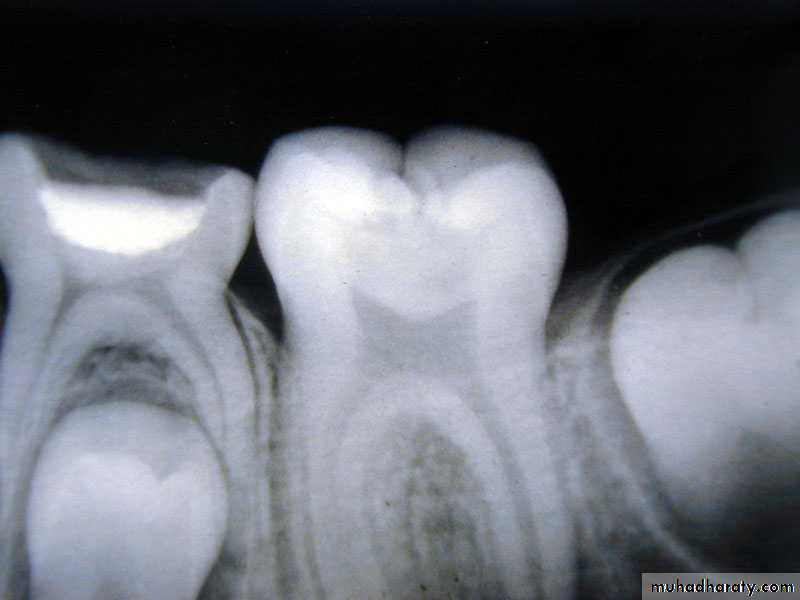

Pulps of Primary Teeth

Relatively larger

Pulp horns are closer to the outer surface

Great variation in size and location

Mesial pulp horn is higher

Pulp chamber shallow

Usually a pulp horn under each cusp

Average dimension of primary molars from exterior surface to the periphery of the pulp chamber

COLLEGE OF DENTISTRYPulp Therapy:

Pulpotomy:

beware of perforations

Pulpectomy:

Difficult on molars due to tortuous and irregular pulp canals

Beware of tooth buds